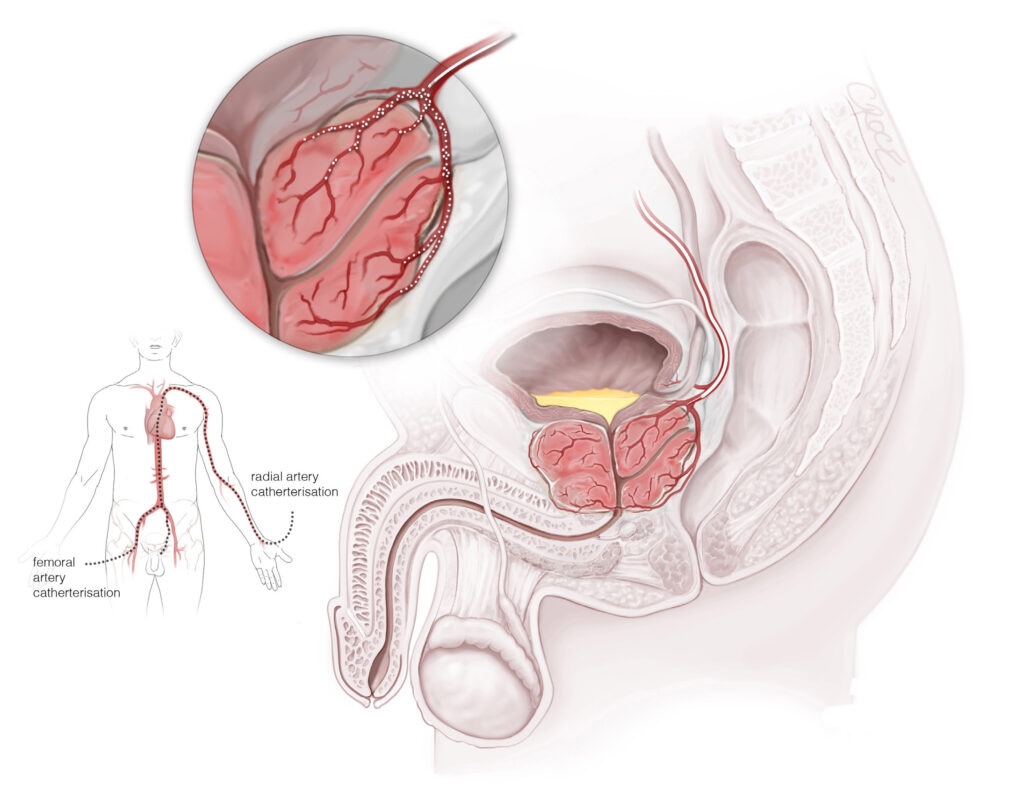

Prostate Artery Embolization

Thanks to remarkable advances in imaging and device technology, we can now reach diseased areas in the body through a tiny needle puncture, and deliver highly targeted treatments with precision, while preserving surrounding healthy tissues. This means less pain, faster recovery, and fewer complications compared to conventional surgery.

After completing my medical training, residency and advanced fellowship in Vascular & Interventional Radiology from the best institutes in the country, I’ve dedicated my career to offering precise, minimally invasive treatments for wide variety of complex conditions like uterine fibroids, thyroid nodules, varicose veins, prostate enlargement, knee joint pains, liver diseases, cancer and many more. Although technology enables precision in Interventional Radiology, but it is compassion, empathy, and ethics that bring meaning to medicine and guide every decision I make in my patient treatment.